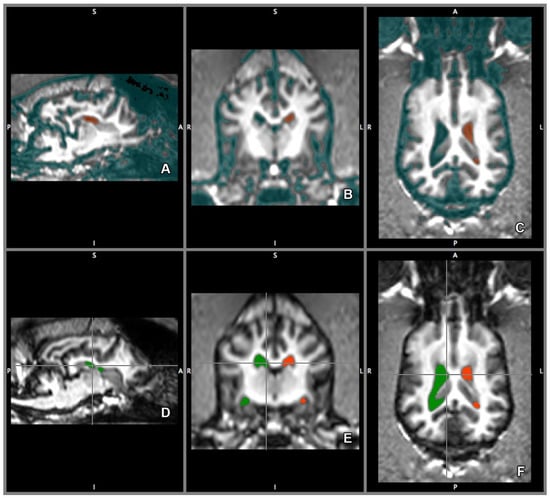

2.5. Morphology and Size of the Measured Brains

3. Results